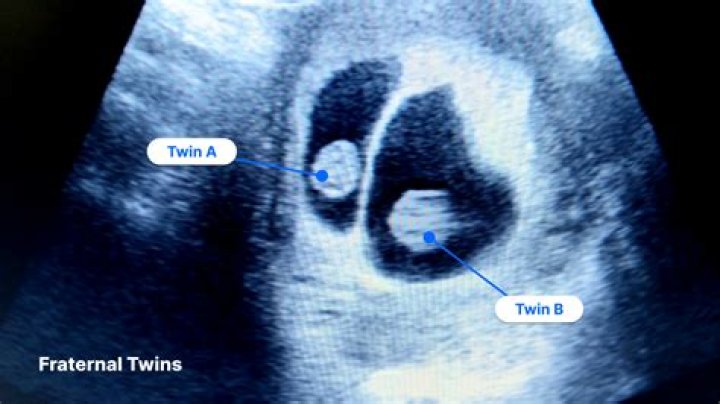

Yes! Twins are defined as children produced in the same pregnancy. Usually they are delivered only a few minutes or hours apart. Twins have been born days and even weeks apart!

The twins were born 11 weeks apart. Such a long interval between twins is rare, but not unheard of. (The world record — twins born 87 days apart — was set in 2012). But it’s not just the separate birthdays that set these twins apart — it’s the fact that each one gestated in a separate womb.

According to Guinness World Records, the longest confirmed interval between the birth of twins is 90 days. Fraternal twins Molly and Benjamin West were born on Jan. 1 and March 30, 1996, in Baltimore.